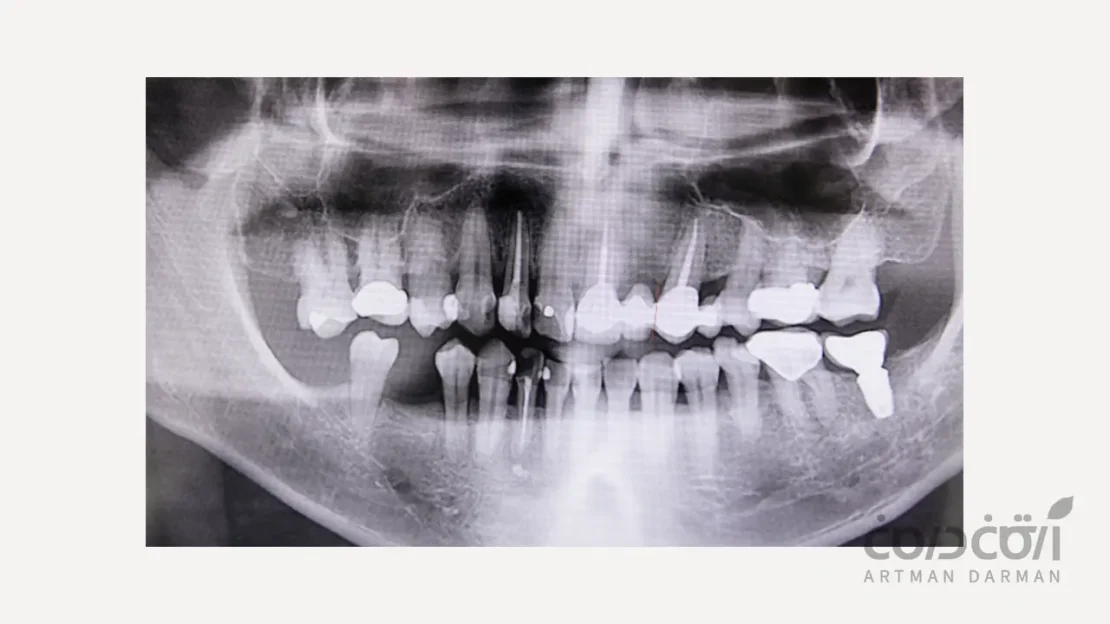

آناتومی و حجم استخوان

با استفاده از اسکن سه بعدی (CBCT)، جراح میزان استخوان باقی ماندهِ پس از کشیدن دندان را به دقت ارزیابی می کند. در این ارزیابی سلامت دیواره های حفره، ضخامت استخوان و فاصله تا ساختارهای اصلی (مانند عصب فک پایین یا سینوس فک بالا) بررسی می شود.